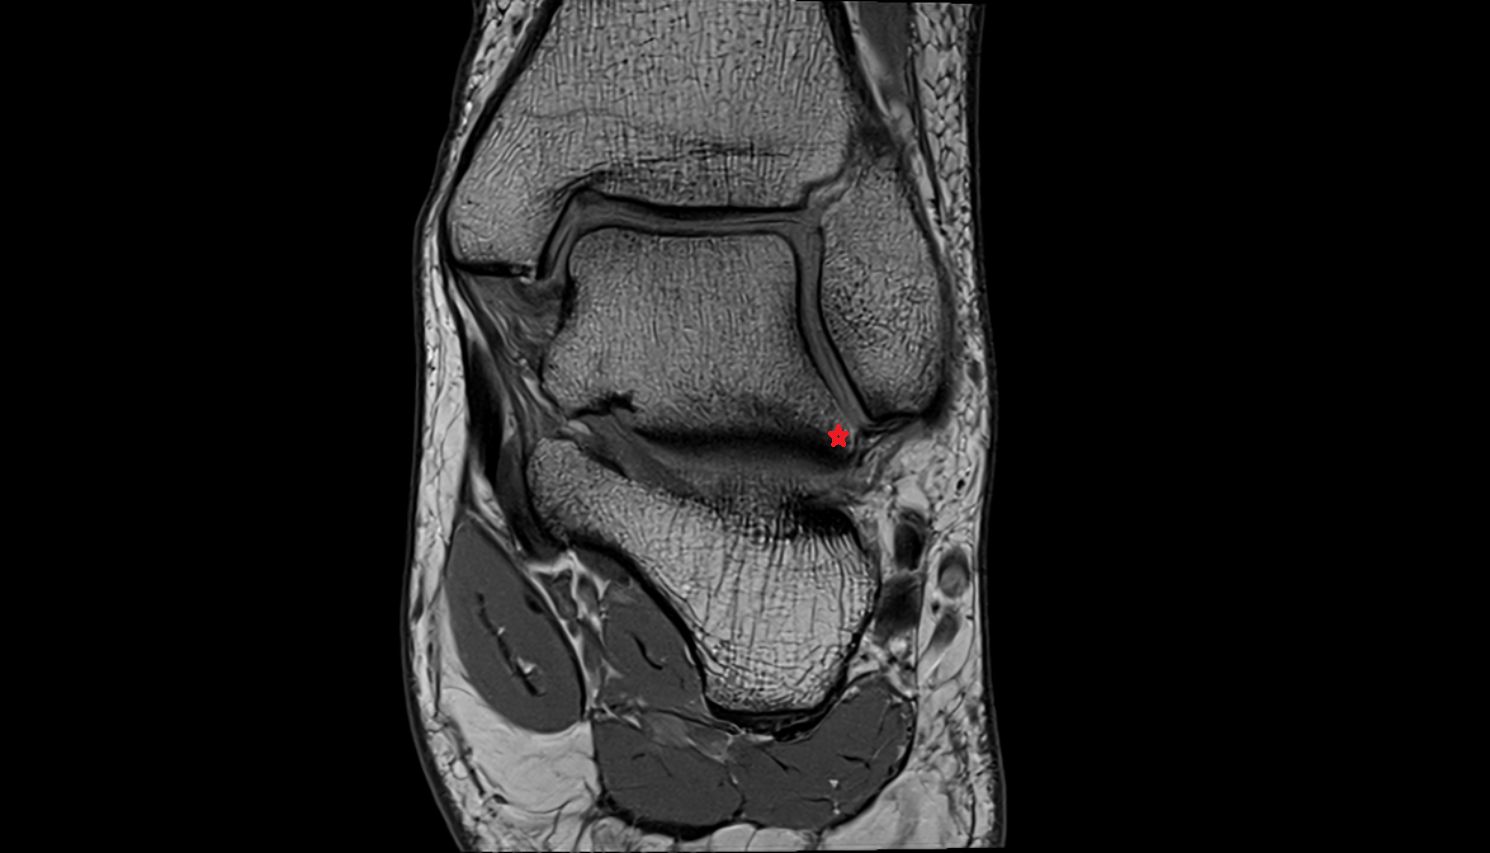

- Medial meniscus

- Lateral meniscus

- Anterior horn of medial meniscus

- Posterior horn of medial meniscus

- Body of medial meniscus

- Anterior root of medial meniscus

- Posterior root of medial meniscus

- Anterior horn of lateral meniscus

- Posterior horn of lateral meniscus

- Body of lateral meniscus

- Anterior root of lateral meniscus

- Posterior root of lateral meniscus